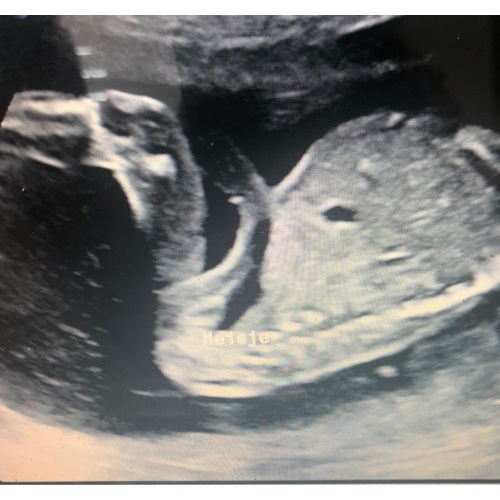

Dit is de foto. Er hangt niks eigenlijk dusja..

Dit is de foto. Er hangt eigenlijk ook niks maar ik zie geen streepjes of ik kijk verkeerd!

Net boven het woord meisje lijk ik het 'hamburgertje' van een meisje te zien. Ik heb eenzelfde soort foto, alleen dan van een jongen en iets meer bovenaf. Je ziet beide beentjes en op het buikje het piemeltje.

Ja inderdaad. Het is een foto van de zijkant zei ze. Ik denk dat ik het gewoon moet gaan geloven! Piemeltje is indd op de buik bij jou foto.

Dit is de foto. Het is van de zijkant genomen. Mischien moet ik het maar geloven omdat er niks hangt.. maar ik heb zo een slecht buik gevoel. Maarja ik kan het ook echt mis hebben.